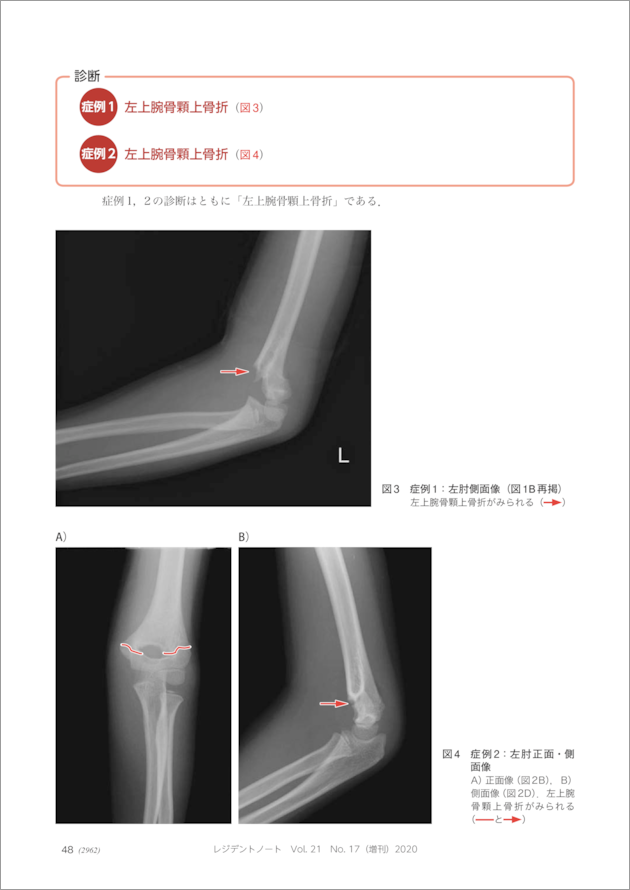

【最安値】 レジデントノート増刊 Vol.21 No.17 骨折を救急で見逃さない 医学一般